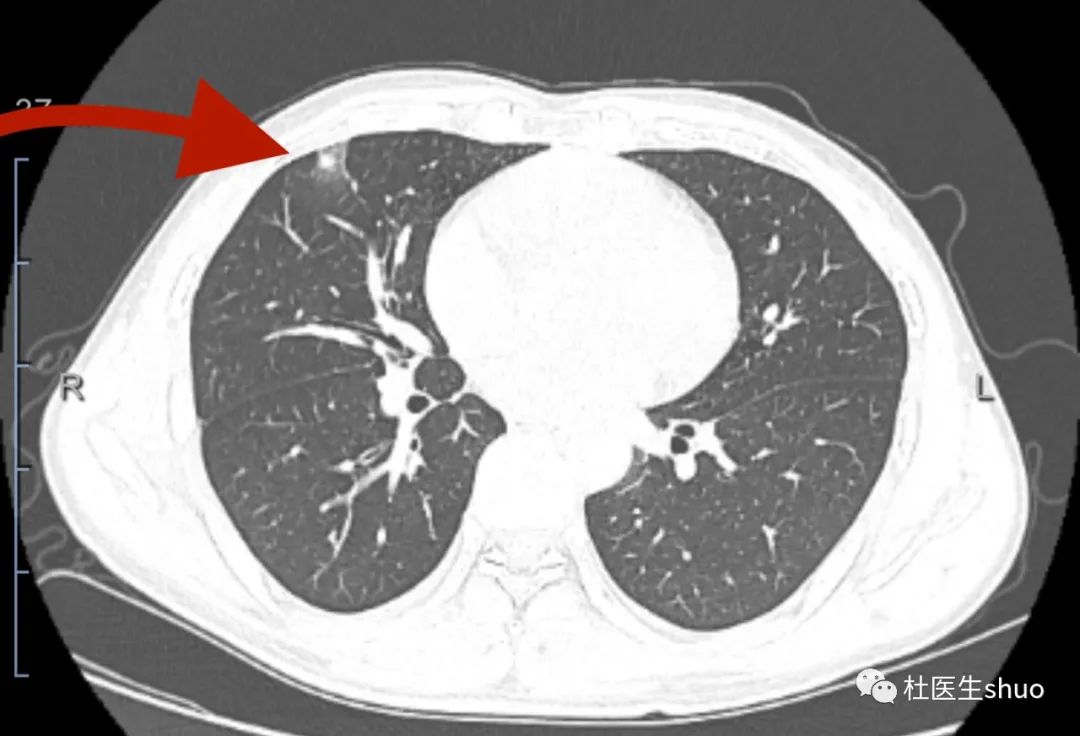

54岁女性左肺上叶部分实性结节

这几位患者都是部分实性结节,切除后都是肺腺癌,查出肺结节需重视,而3-4毫米的肺结节则不必过于担心。